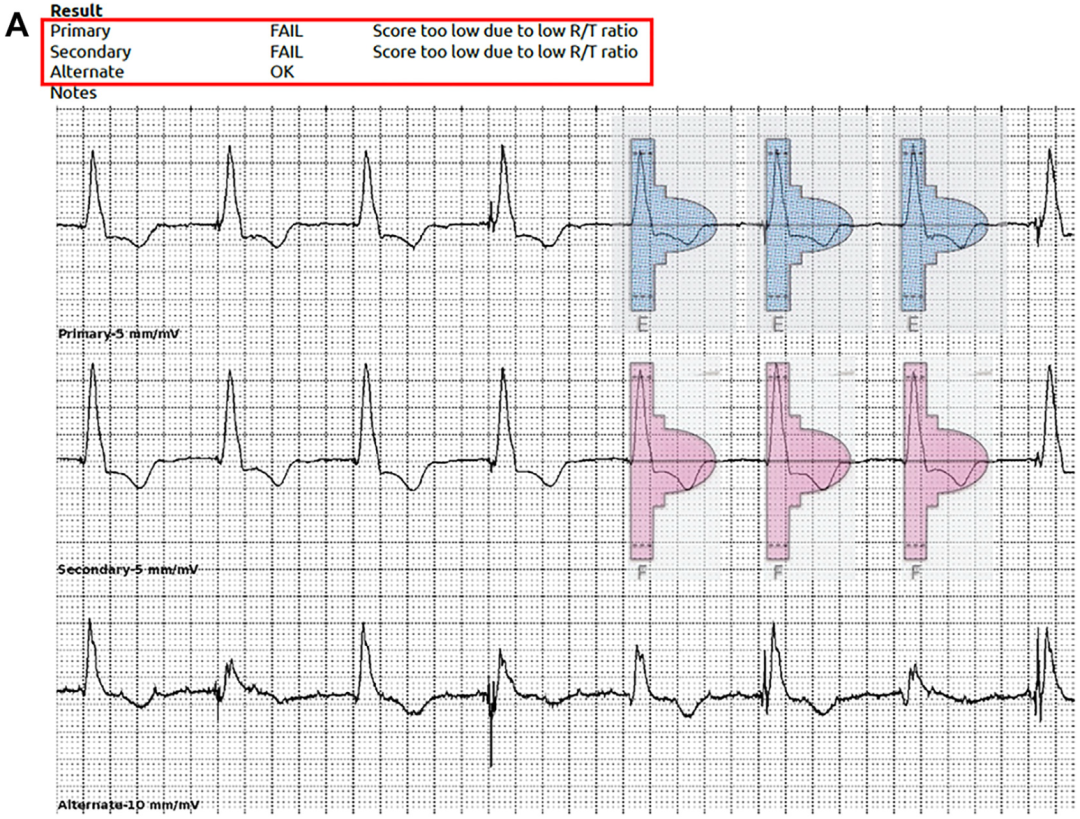

使用S-ICD程控仪的自动筛查工具评估该患者时,因R/T比值过低而未能通过(图A);

图A S-ICD程控仪自动筛查评估未通过

但后通过手动筛查工具评估,发现Primary向量和Secondary向量均显示出合理的电图形态,因此,最终将S-ICD植入(图B);

术中,Primary、Secondary向量均显示QRS感知良好,无T波过感知现象;使用Secondary向量成功诱发并终止心室颤动,一次65焦耳电击即成功复律。